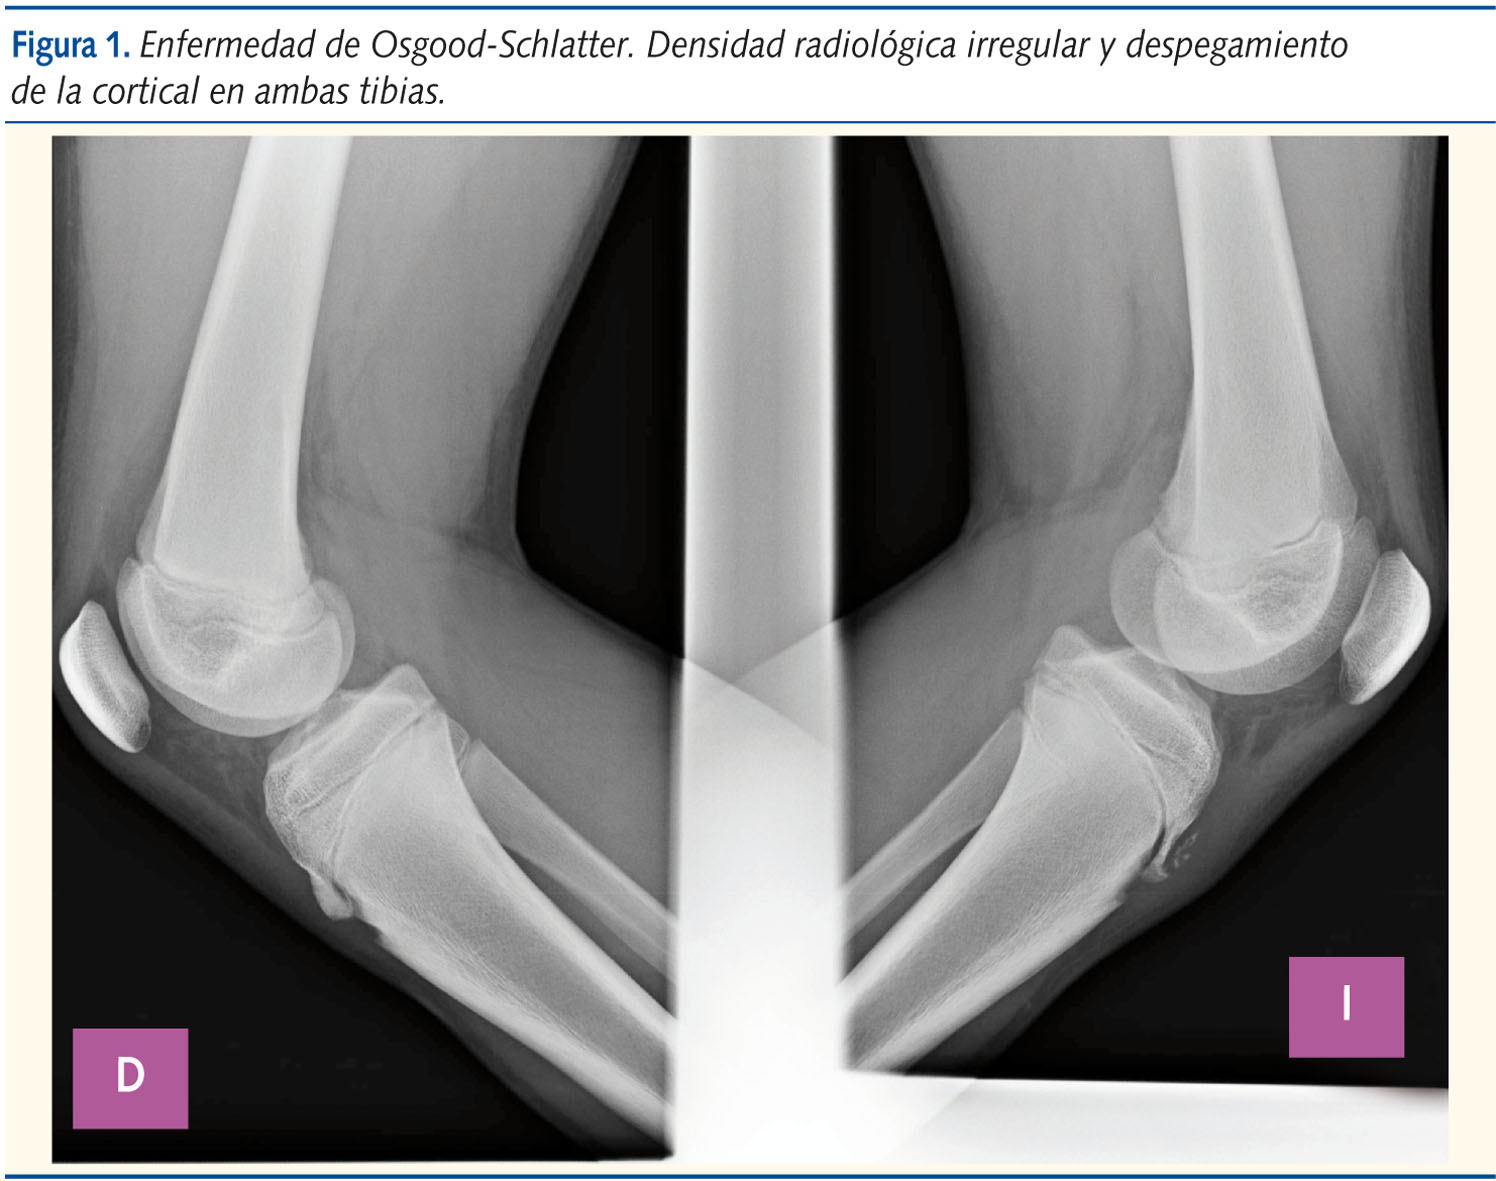

● Apofisitis tibial ● Enfermedad de Osgood-Schlatter ● OsteocondrosisPaciente de 13 años de edad que acude al Servicio de Urgencias Pediátricas de nuestro hospital, aquejado de dolor en ambas rodillas de un año de evolución (más acusado en el lado izquierdo), con empeoramiento progresivo hasta hacerse prácticamente invalidante en la última semana. El dolor es de características mecánicas, y empeora claramente con la actividad física, especialmente cuando juega al baloncesto. La exploración física muestra una tumoración dolorosa sobre ambas tuberosidades tibiales anteriores (TTA), sin calor ni rubor asociados. Sin datos de inestabilidad o derrame articular. Se solicitó estudio radiológico (figuras 1 y 2), en cuya proyección lateral se objetivó una discontinuidad de la tuberosidad tibial anterior, junto con heterogeneidad en la densidad de la misma y fragmentación ósea. Todo ello es compatible con la enfermedad de Osgood-Schlatter (EOS).

El diagnóstico de esta entidad es esencialmente clínico, si bien el examen radiológico permite descartar otros orígenes del dolor. Los hallazgos se exponen en la tabla 23,5.